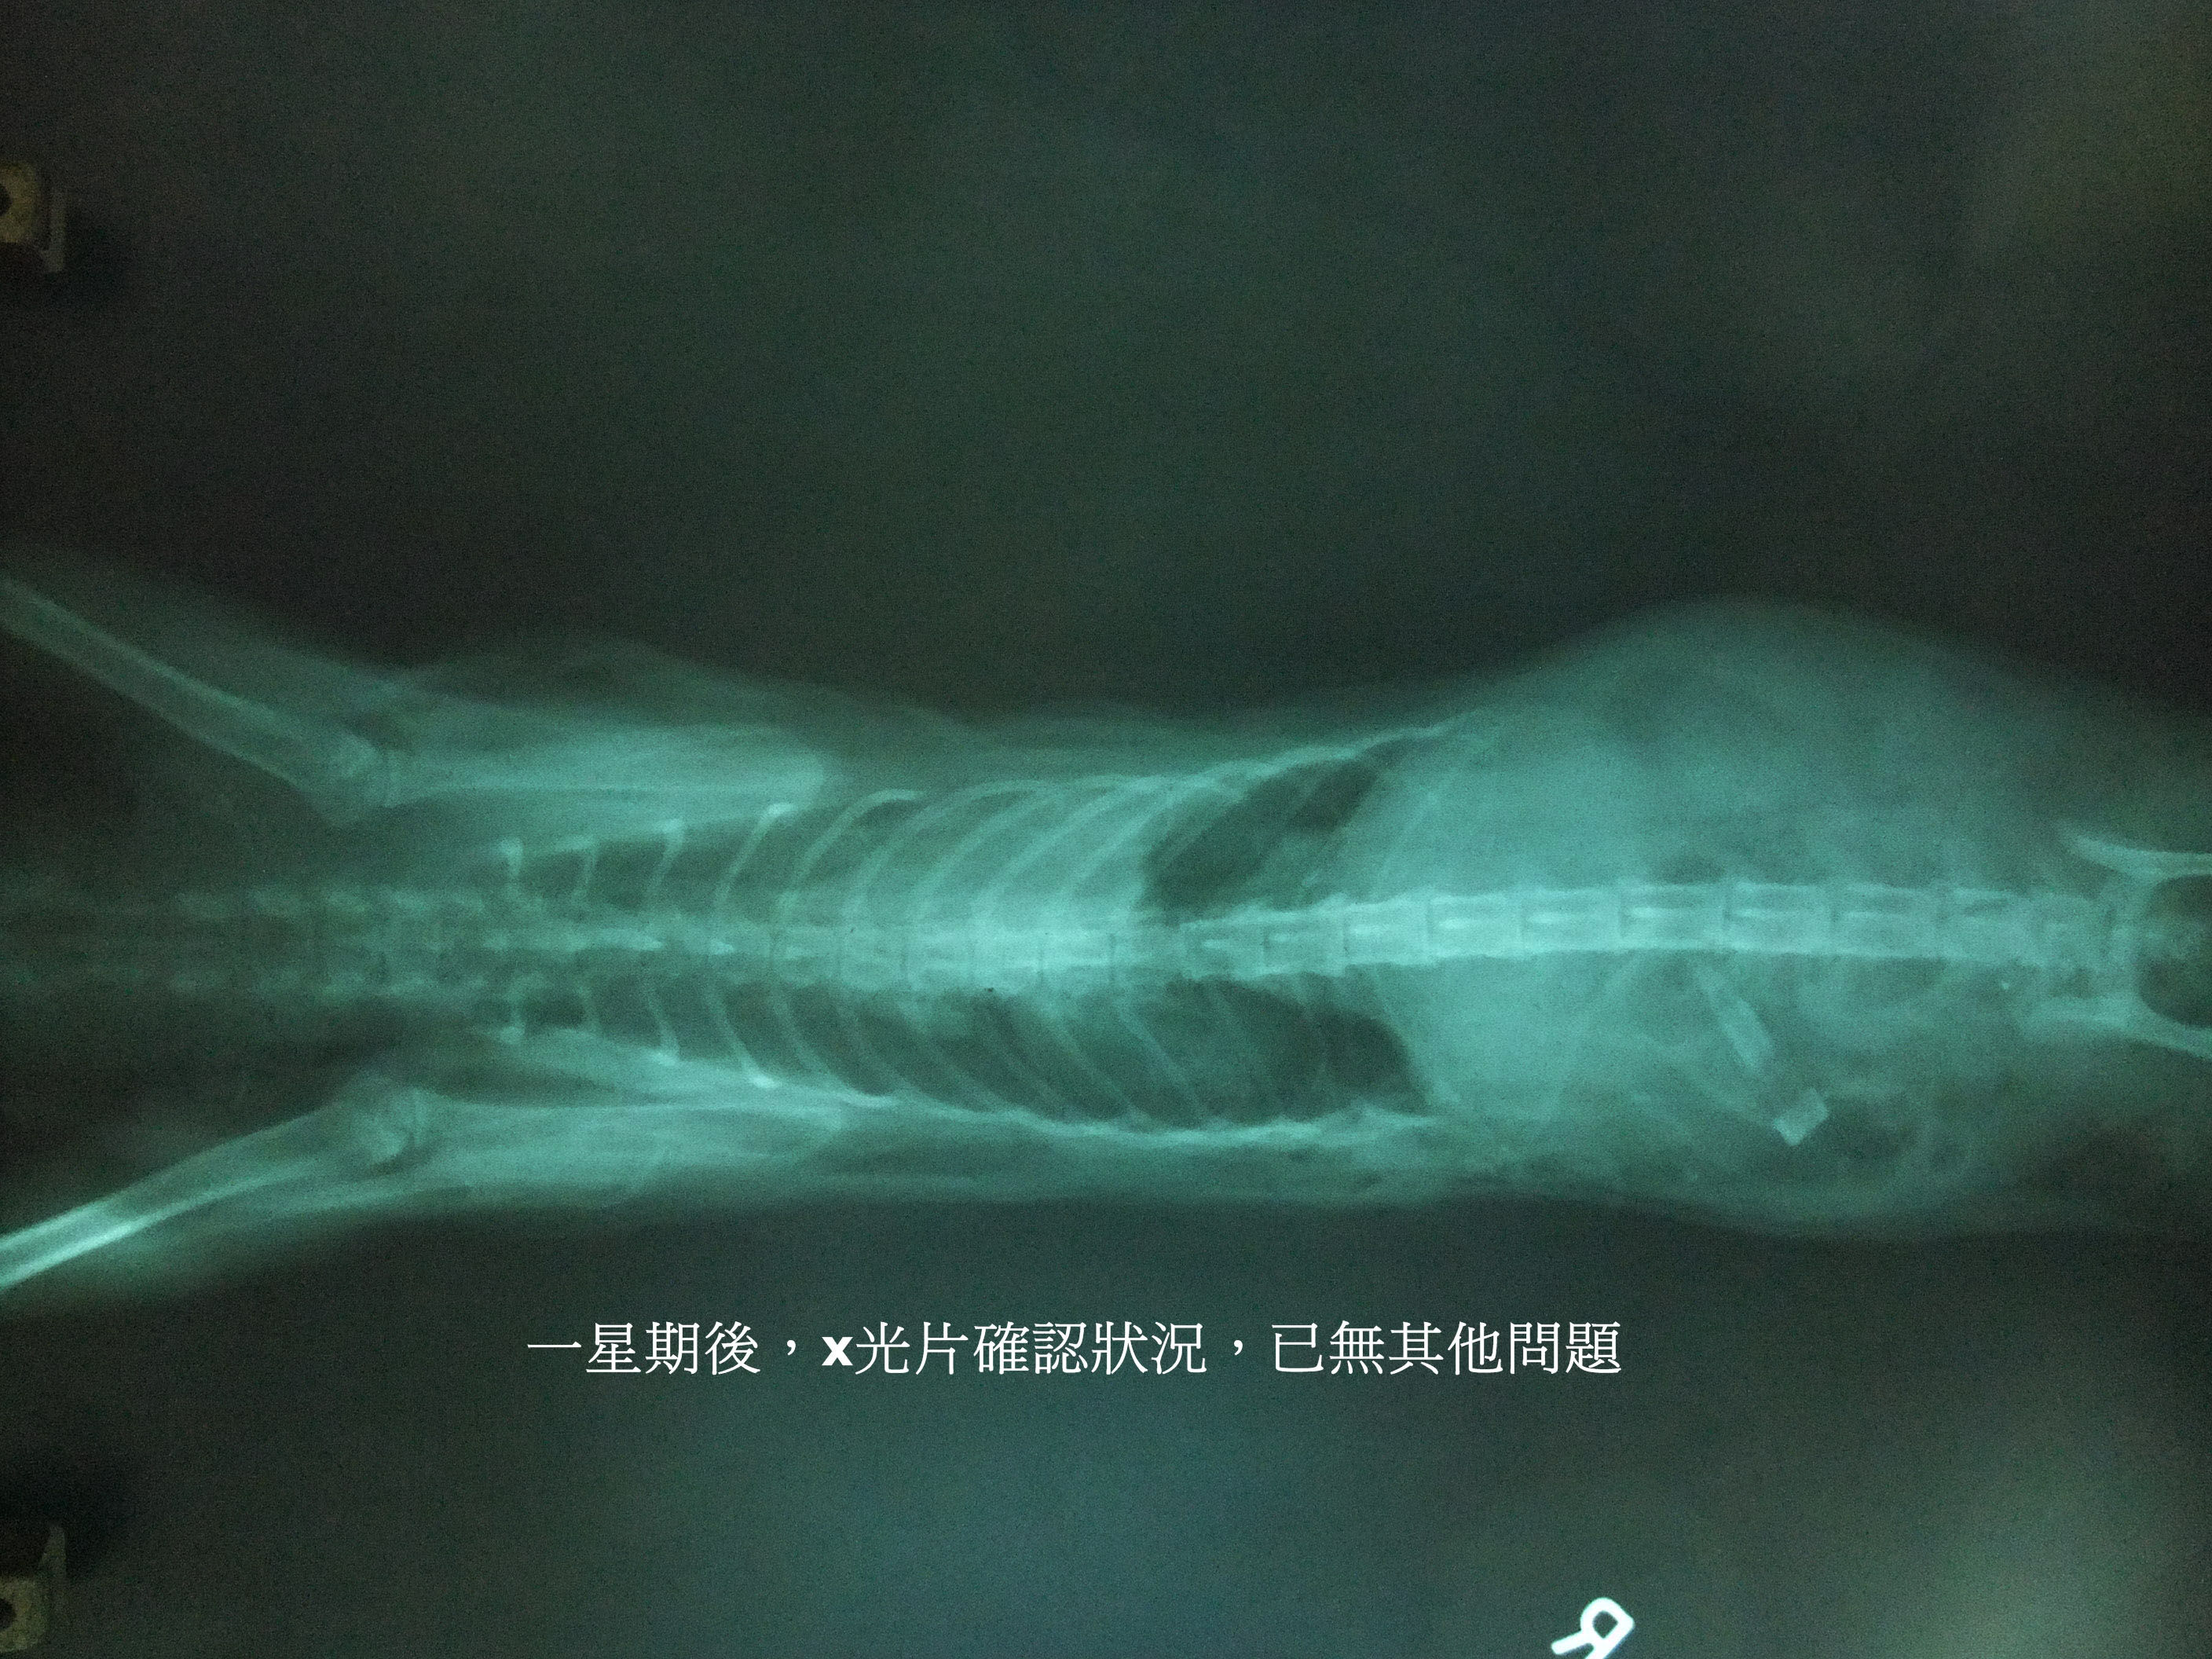

醫生的X光片顯示,第十二根肋骨斷裂並產生氣胸,馬上緊急手術。因發現的早,所以貓咪很幸運的撿回一條命。

動物近況說明: 捲耳貓在醫院內很沉默,到目前為止不曾聽到她開口發出聲音過,大大的雙眼有著滿滿的疑惑,似乎不知道自己的明天何去何從,讓人心疼...

貓咪休養一陣子後會為她找個家,幫這個心靈受創的孩子找愛她的爸媽。